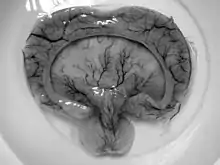

Holoprosencephaly (HPE) is a cephalic disorder in which the prosencephalon (the forebrain of the embryo) fails to develop into two hemispheres, typically occurring between the 18th and 28th day of gestation.[1] Normally, the forebrain is formed and the face begins to develop in the fifth and sixth weeks of human pregnancy. The condition also occurs in other species.

When the embryo's forebrain does not divide to form bilateral cerebral hemispheres (the left and right halves of the brain), it causes defects in the development of the face and in brain structure and function.